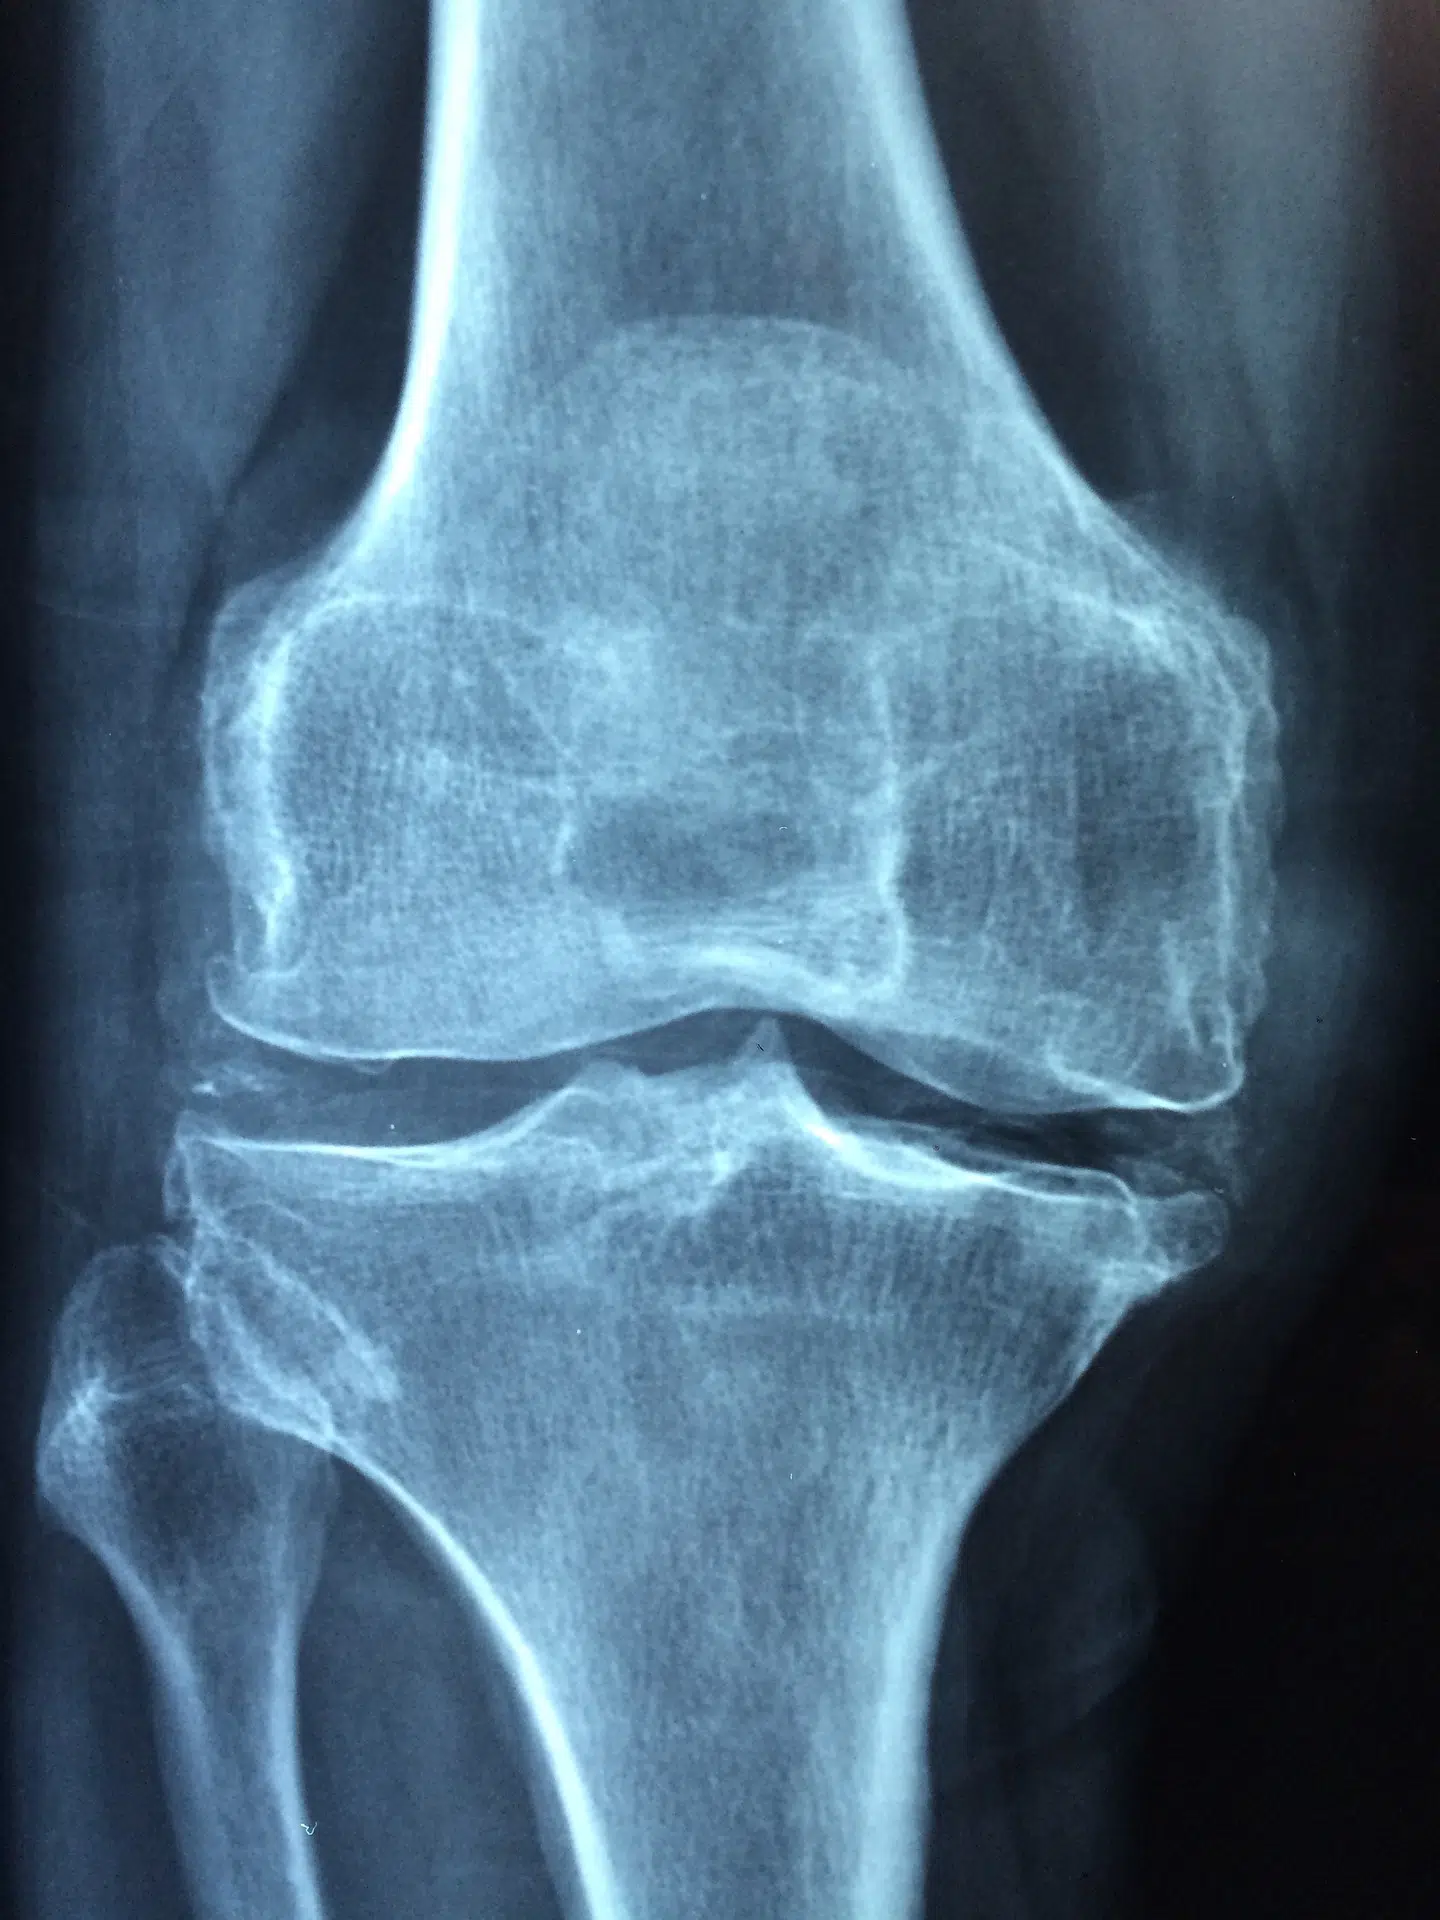

Quand les traitements précédents n’offrent plus de soulagement suffisant, l’option chirurgicale peut s’imposer. Deux interventions se distinguent : l’arthroscopie et l’arthroplastie.

L’arthroscopie permet de visualiser l’intérieur de l’articulation grâce à une petite caméra. Elle offre la possibilité de diagnostiquer et de traiter certaines lésions de façon peu invasive. L’arthroplastie, en revanche, va plus loin : elle consiste à remplacer une articulation usée par une prothèse neuve. Ce sont souvent les hanches ou les genoux qui bénéficient de cette renaissance mécanique.